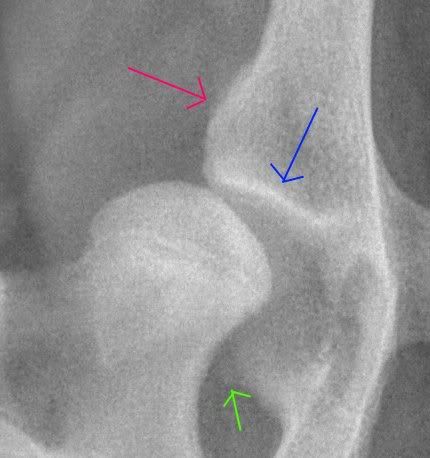

Als we even inzoomen op de rechter heup:

Dan is er ondanks de zeer jonge leeftijd al artrosevorming te zien. Het blauwe pijltje geeft sclerose aan: het lichaam depositeert meer mineraal om het bot te versterken, vandaar de witte lijn. Het roze pijltje geeft nieuw gevormd bot aan, dit is een poging het gewricht te stabiliseren. Bij het groene pijltje lijkt er al sprake te zijn van een osteofyt.

Deze hond is nu nog een geschikte kandidaat voor een bekkenkanteling. Zonder die ingreep zal deze hond ongetwijfeld ernstig last krijgen. Ondanks dat er al wat artrose is zijn de vooruitzichten nu nog goed. Er moet niet gewacht worden want als deze hond pas op de leeftijd van een jaar geopereerd wordt dan heeft zelfs de bekkenkanteling waarschijnlijk amper zin meer omdat het gewricht dan waarschijnlijk al verwoest is door artrose.

Marjoleine: het is absoluut ondenkbaar dat deze hond ooit nog A of B of zelfs C heupen zou krijgen. Deze heupen zijn al heel slecht, en worden alleen nog maar slechter. Je hoeft bepaald geen specialist te zijn om dat vast te stellen, ook een gewone dierenarts hoeft m.i. dus niet 'terughoudend' te zijn in de diagnose. Ik ben heel benieuwd of jij wel fotos kunt plaatsen van de gevallen die eerst bekkenkanteling zouden zijn maar vervolgens een A gekregen hebben. Kijken of ik snap wat daar fout gegaan is.

Het manken van deze teef kwam overigens NIET door de heupdysplasie, maar door groeipijnen..... maar dankzij de groeipijnen is de röntgenfoto genomen waardoor de HD mogelijk nog behandeld kan worden. Geluk bij een ongeluk dus.